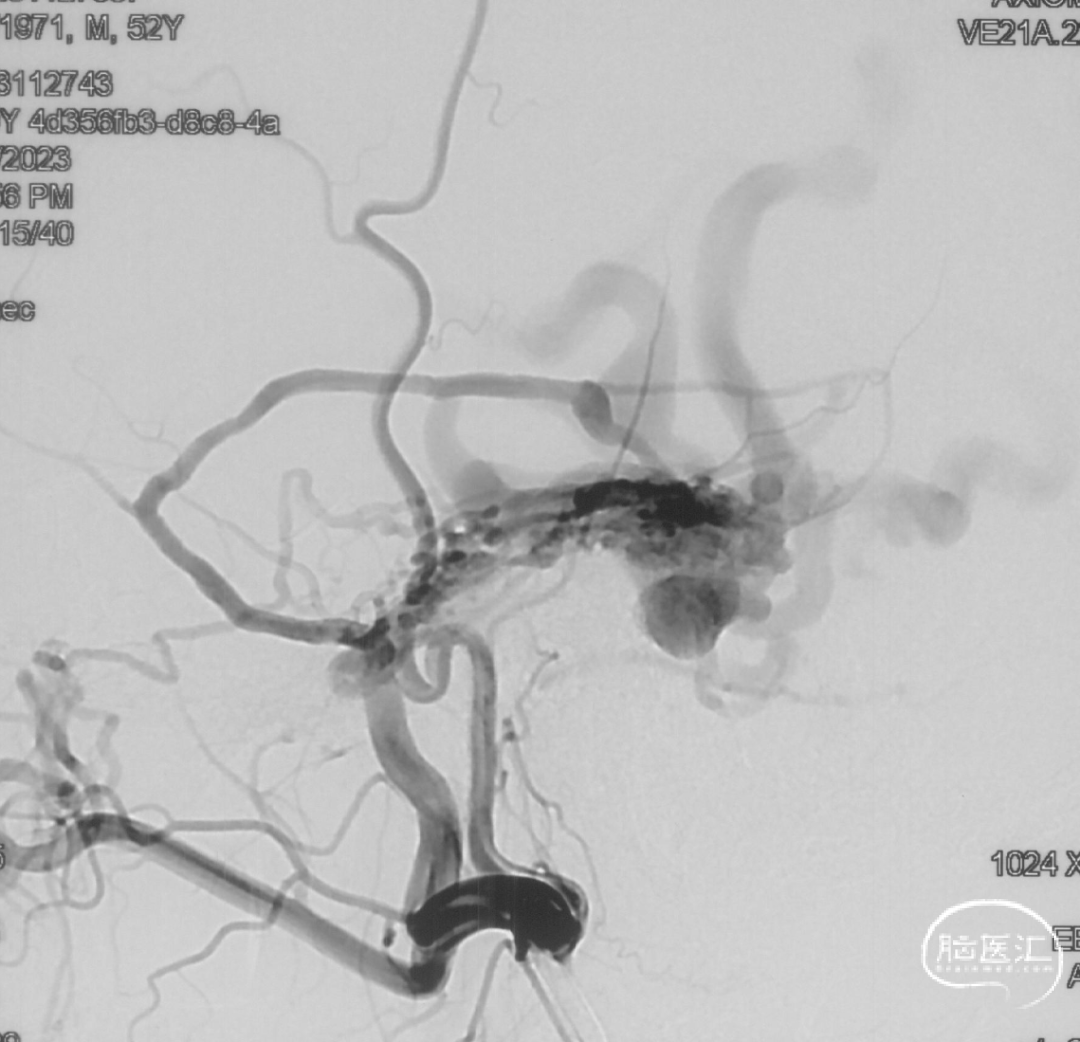

证实为TDAVF,为岩上窦型。R-ECA正侧位见右侧脑膜中动脉分支、枕动脉分支、颞浅动脉分支向瘘口供血,经幕上迂曲扩张的静脉、中脑周围静脉、基底静脉向深部静脉引流。

R-ICA正侧位见右侧脑膜垂体干向瘘口供血

L-ICA正侧位见左侧脑膜垂体干分支向瘘口供血

L-ECA正侧位未见向瘘口供血

L-VA、R-VA正侧位右侧小脑上动脉脑膜支向瘘口供血

结构分析:右侧天幕区硬脑膜动静脉瘘,瘘口位于右侧岩上窦,供血动脉主要包括右侧脑膜中动脉的颞支、岩鳞支,右侧枕动脉分支,右侧颞浅动脉分支,双侧脑膜垂体干,右侧小脑上动脉脑膜支,经幕上迂曲扩张的静脉、中脑周围静脉、基底静脉向深部静脉引流,引流静脉起始部见扩张的静脉球。Cognard分型IV型,Borden分型III型,Lawton分型IV型(岩上窦型)。